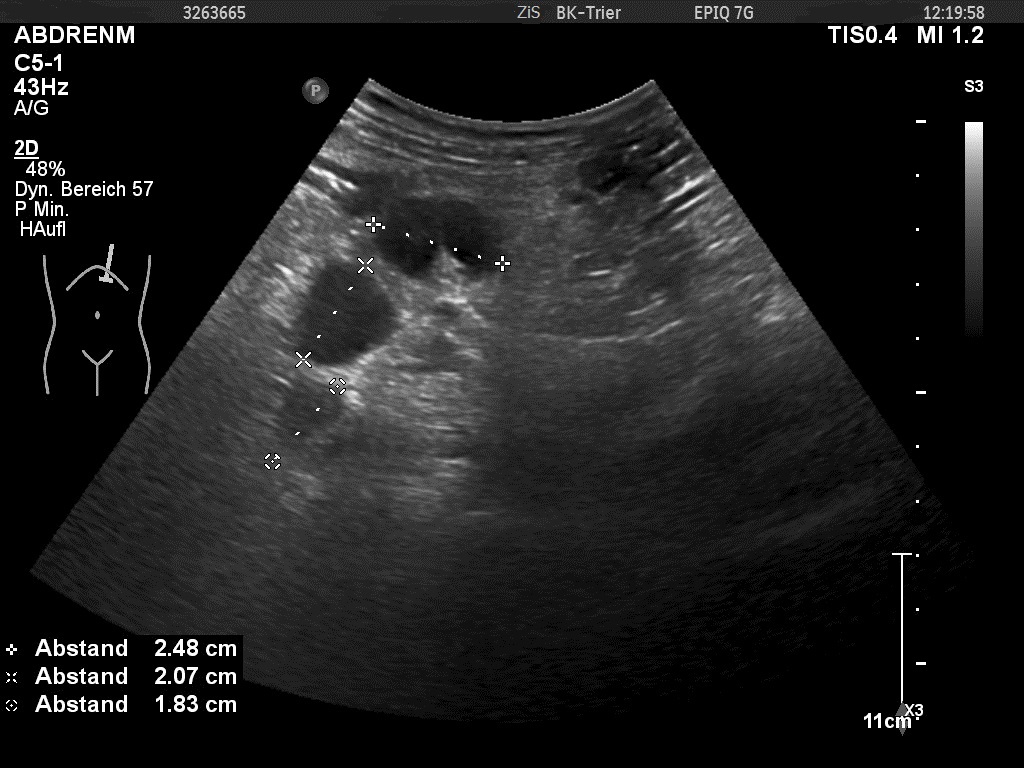

Sonography also revealed enlarged hypoechoic aortocaval and mesenteric lymph nodes. These lymph nodes showed a homogenous and hypoechoic parenchyma, with no echogenic hilar structures visible. These nodes measured up to 3.8 cm in maximal diameter, the short axis of the greatest lymph node was 2,4cm and the cortical thickness 2cm.